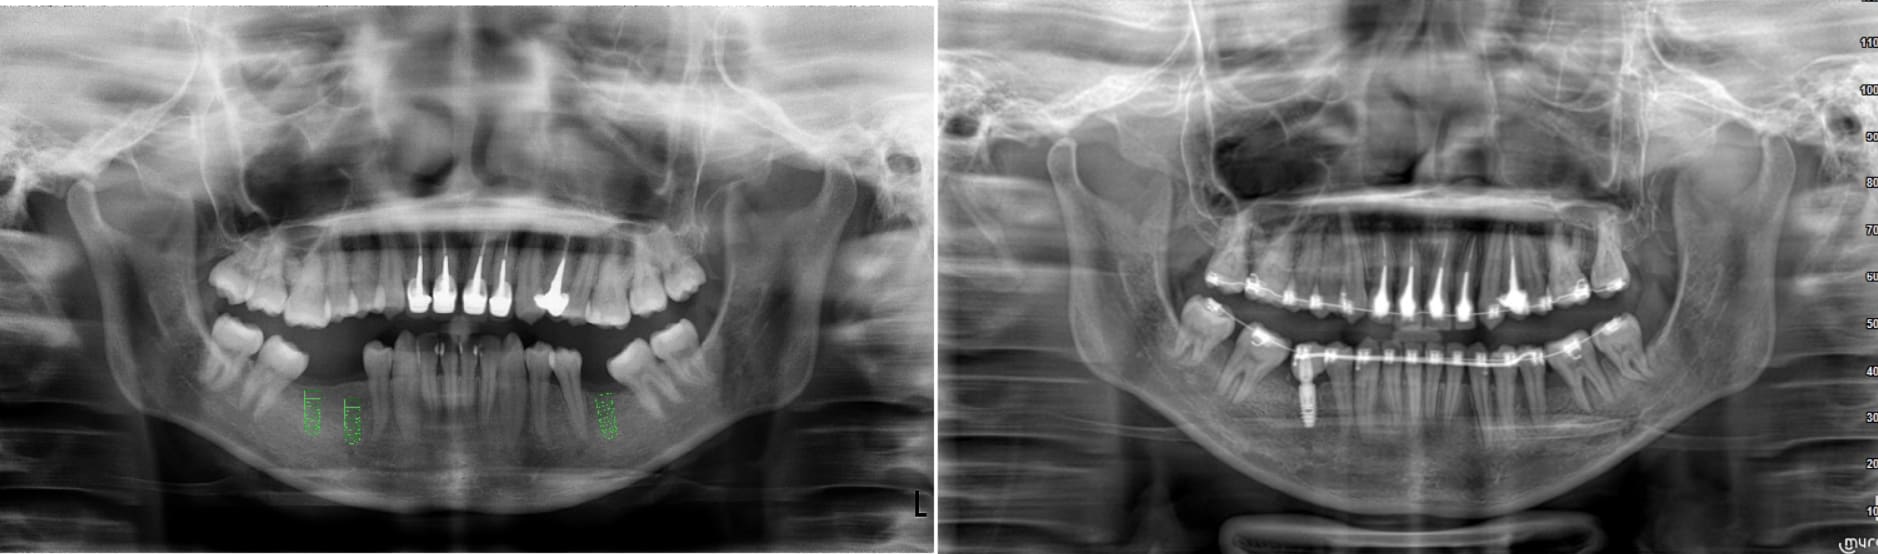

J'aurais besoin de votre avis éclairé dans la gestion de cet édentement 16 17.

La 18 est mésialée et regarde un peu en vestibulaire.

J'ai extrait la 16 suite à une fracture de racines et une infection paro.

Et maintenant se pose le problème du replacement de 16 et 17.

Que faire:

1) implant 16 et on laisse le diastème 16 / 18

2) extraction de 18 et un bridge 16 17 18 sur 2 implants 16 18.

Quel est votre avis?